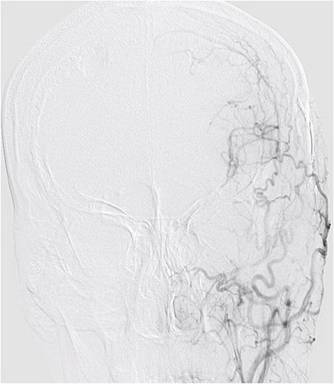

入院后,患者完善了所有检查;TCD提示:左侧大脑中动脉中度狭窄;右侧大脑中动脉血流减慢;左侧大脑前动脉及大脑后动脉血流速度增快;右侧大脑后动脉血流速度减慢。颅脑MRI-ASL提示:左侧额顶叶灌注低(如图2)。DSA影像显示:烟雾病(如图3)双侧颈内动脉末端闭塞,颅底可见烟雾状血管生成部分代偿供血。

图3,术前DSA可见颈内动脉末端闭塞

外六科吴杰主任、闫学强主治医生对患者进行了综合评估:患者3个月前为左侧脑室出血,且目前左侧半球供血不足比右侧显著,医生拟先实施左侧脑内血管重建术,二期实施右侧脑内血管重建术。几日后,患者在全麻下接受左侧颞浅动脉-大脑中动脉搭桥术,医生采取左侧额颞直切口,长约175px,创伤小(术中如图4);术中医生利用荧光造影,可清晰见到吻合血管通畅(如图5)。整个手术过程顺利,患者术后恢复良好,复查DSA,吻合血管通畅,颅内血供明显改善(如图6),并无神经功能缺失。目前患者已痊愈出院。

图6,术后复查DSA,吻合血管通畅,颅内供血改善